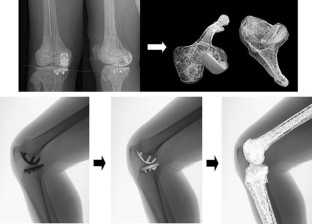

Seventeen osteoarthritic knees were tested before and after unicompartmental arthroplasty using a three-dimensional to two-dimensional registration technique tracking the transepicondylar axis to calculate translation and rotation of this axis. Results were compared for the seventeen knees before and after arthroplasty and were compared to the normal knee as measured in our previous study.

Fig. 2